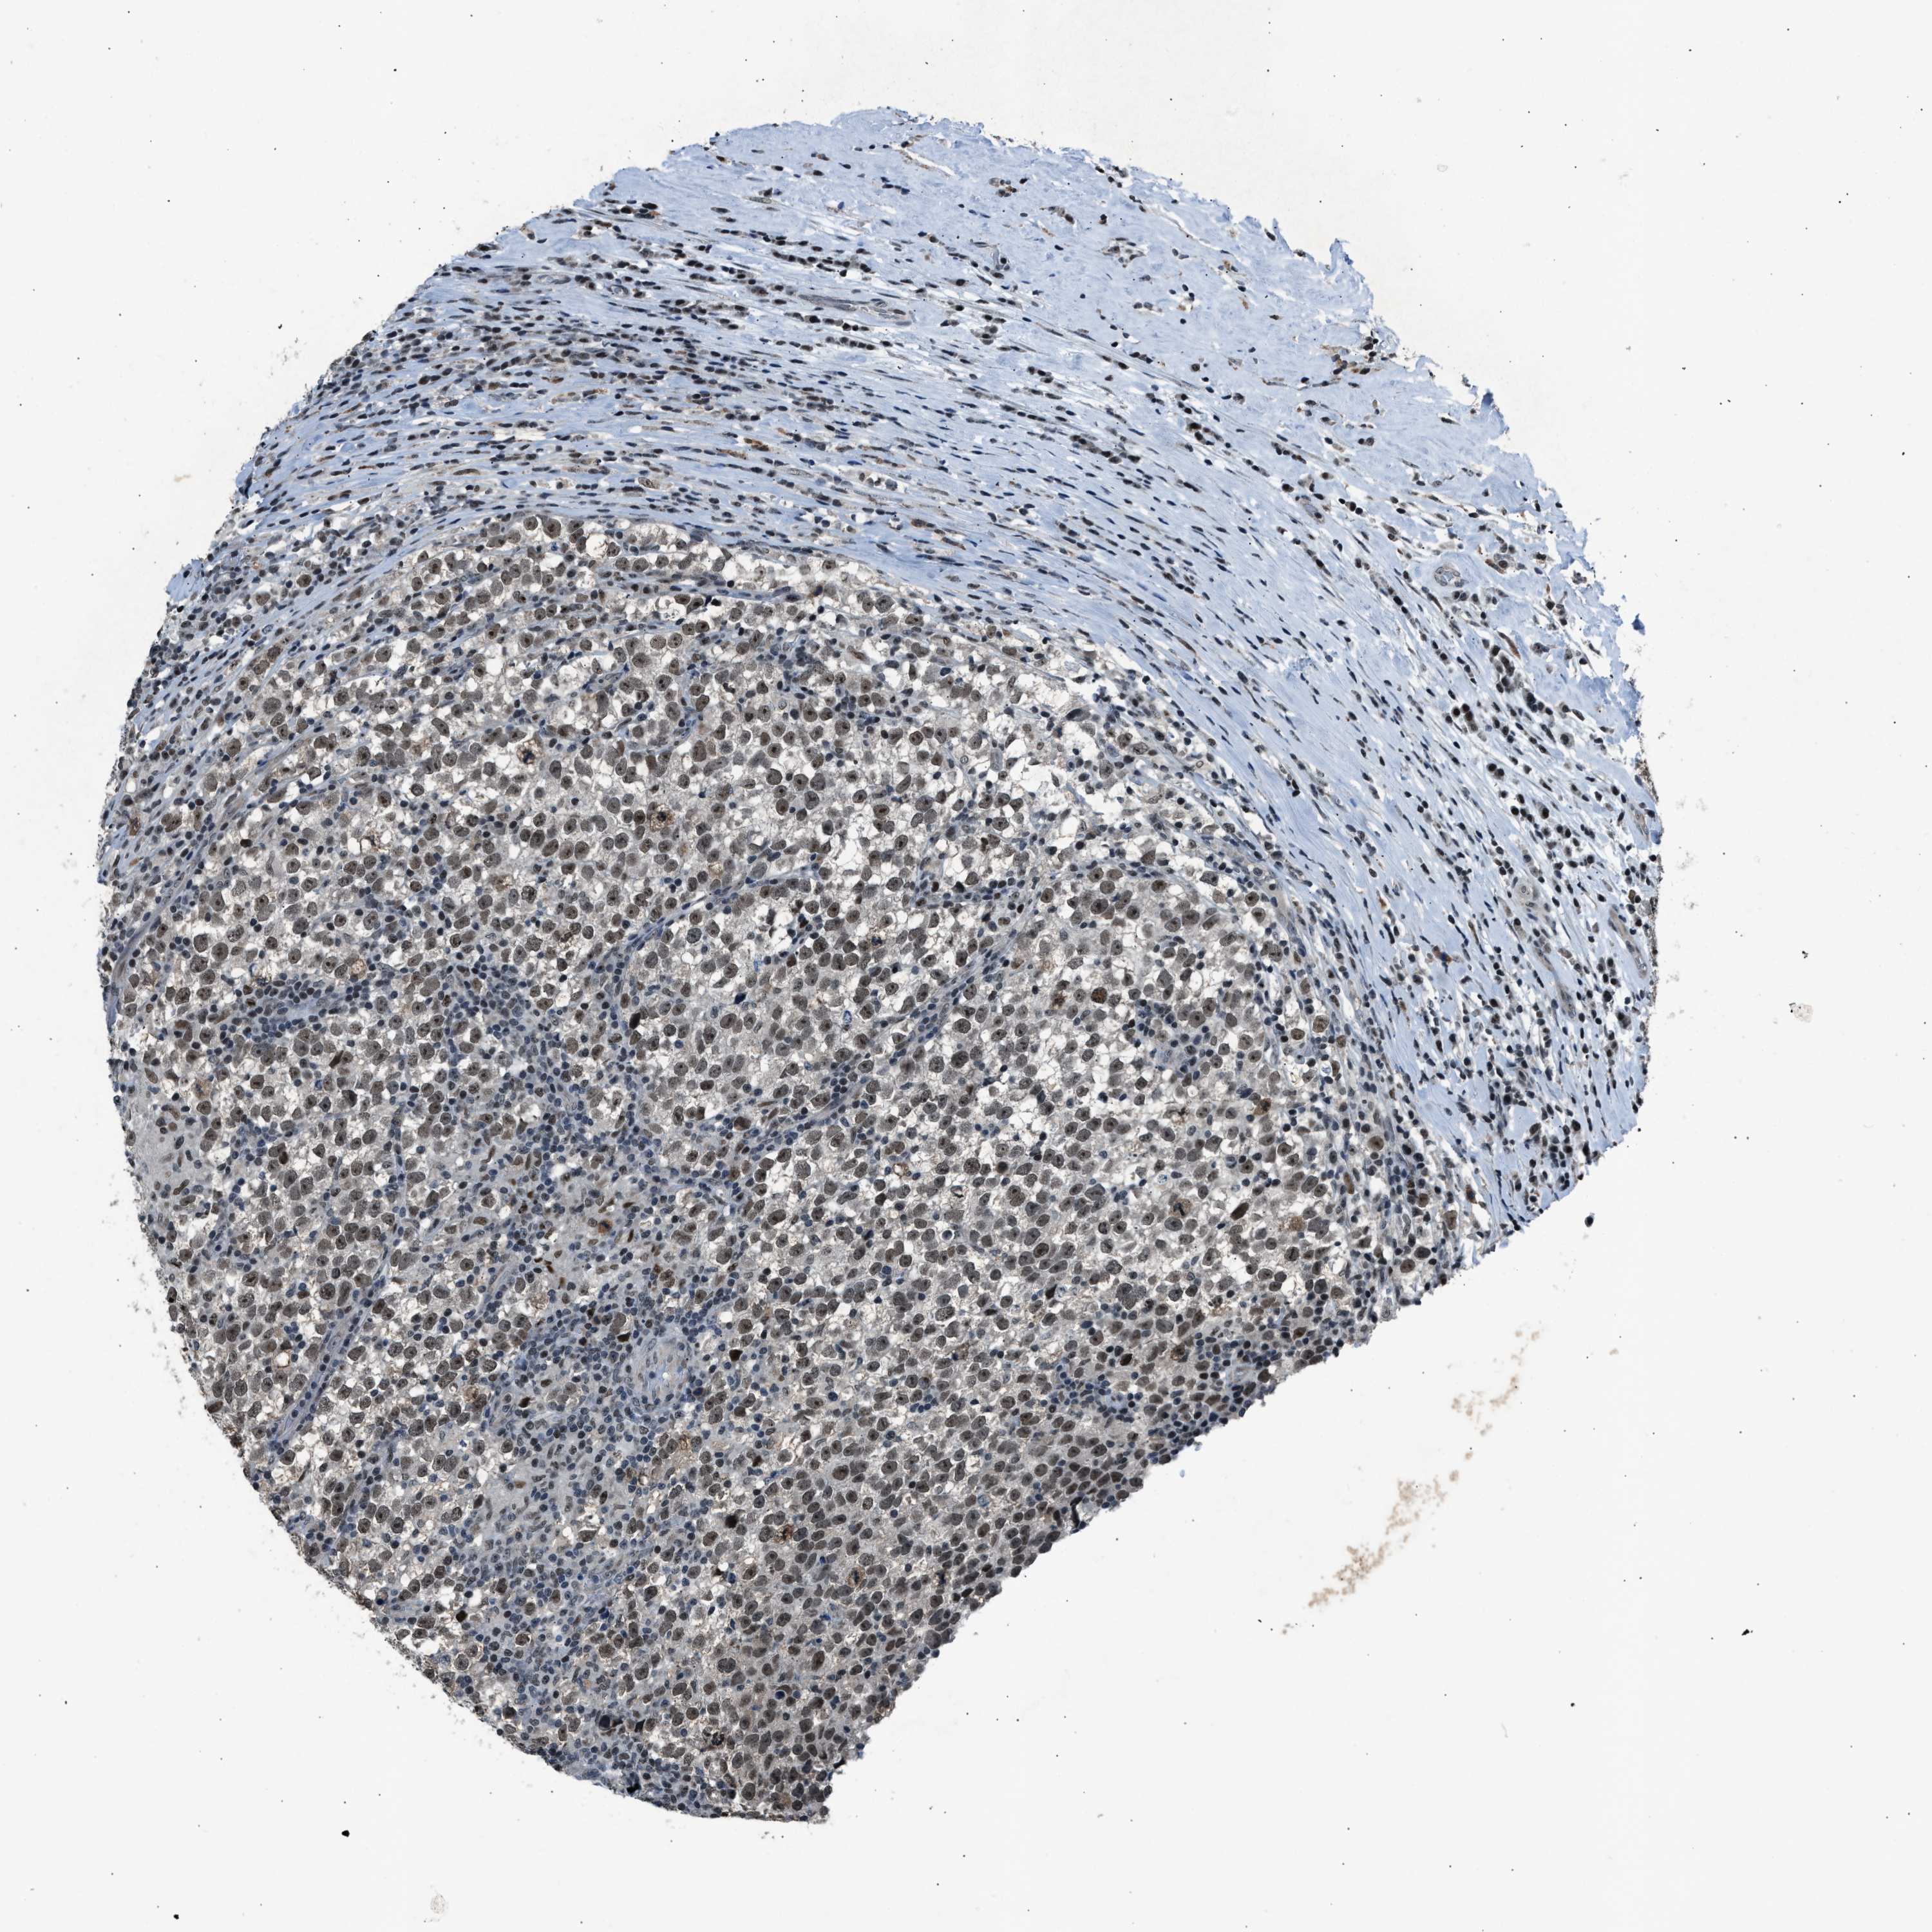

TESTIS CANCER - Protein expressioni

A mouse-over function shows sample information and annotation data. Click on an image to view it in a full screen mode. Samples can be filtered based on level of antibody staining by selecting one or several of the following categories: high, medium, low and not detected. The assay and annotation is described here.

Note that samples used for immunohistochemistry by the Human Protein Atlas do not correspond to samples in the TCGA dataset.

Antibody stainingi

Antibody staining in the annotated cell types in the current human tissue is reported as not detected, low, medium, or high, based on conventional immunohistochemistry profiling in selected tissues. This score is based on the combination of the staining intensity and fraction of stained cells.

Each image is clickable and will lead to virtual microscopy that enables deeper exploration of all samples and also displays staining intensity scores, fraction scores and subcellular localization as well as patient and tissue information for each sample.

Antibody CAB018364

Staining

High

Medium

Low

Not detected

Intensity

Strong

Moderate

Weak

Negative

Quantity

>75%

75%-25%

<25%

None

Location

Nuclear

Cytoplasmic/membranous

Cytoplasmic/membranous,nuclear

Seminoma, NOS